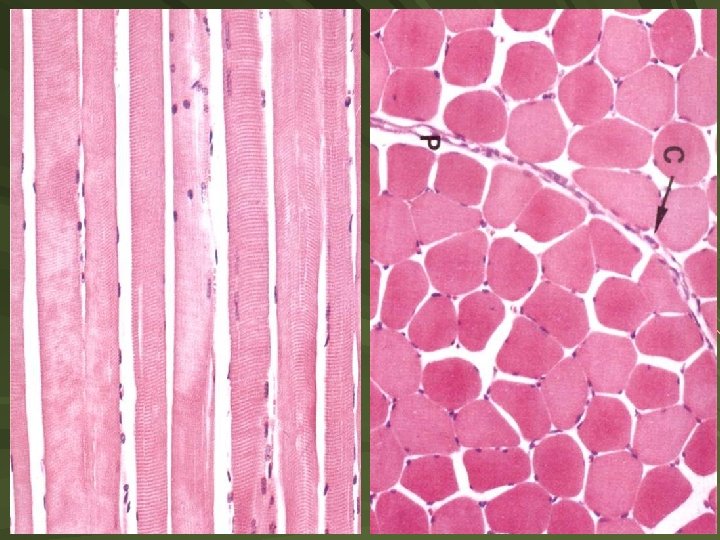

Kosterní sval Rychlá, vůlí ovládaná kontrakce Morfologická jednotka - Syncytium - mnohojaderné svalové vlákno, dlouhé až 30 cm - Jádra syncytia na periferii těsně pod plazmatickou membránou Uspořádání vláken ve svalu: Sval Svazek vláken - fasciculus Svalové vlákno Myofibrily Myofilamenta Sarkomera - uprostřed izotropního úseku se aktinová myoflamenta upínají do Z-linie – mezi Z liniemi sarkomera

ENDOMYSIUM - vazivo kolem svalového vlákna - bazální lamina + retikulární vlákna, kapiláry PERIMYSIUM - kolem fascikulu svalových vláken, řídké kolagenní vazovo EPIMYSIUM – obaluje sval